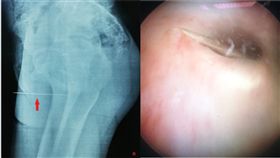

性怪癖?少年「2寸縫衣針插尿道」

突尼西亞當地一間大醫院泌尿科,日前出現一名14歲男孩...